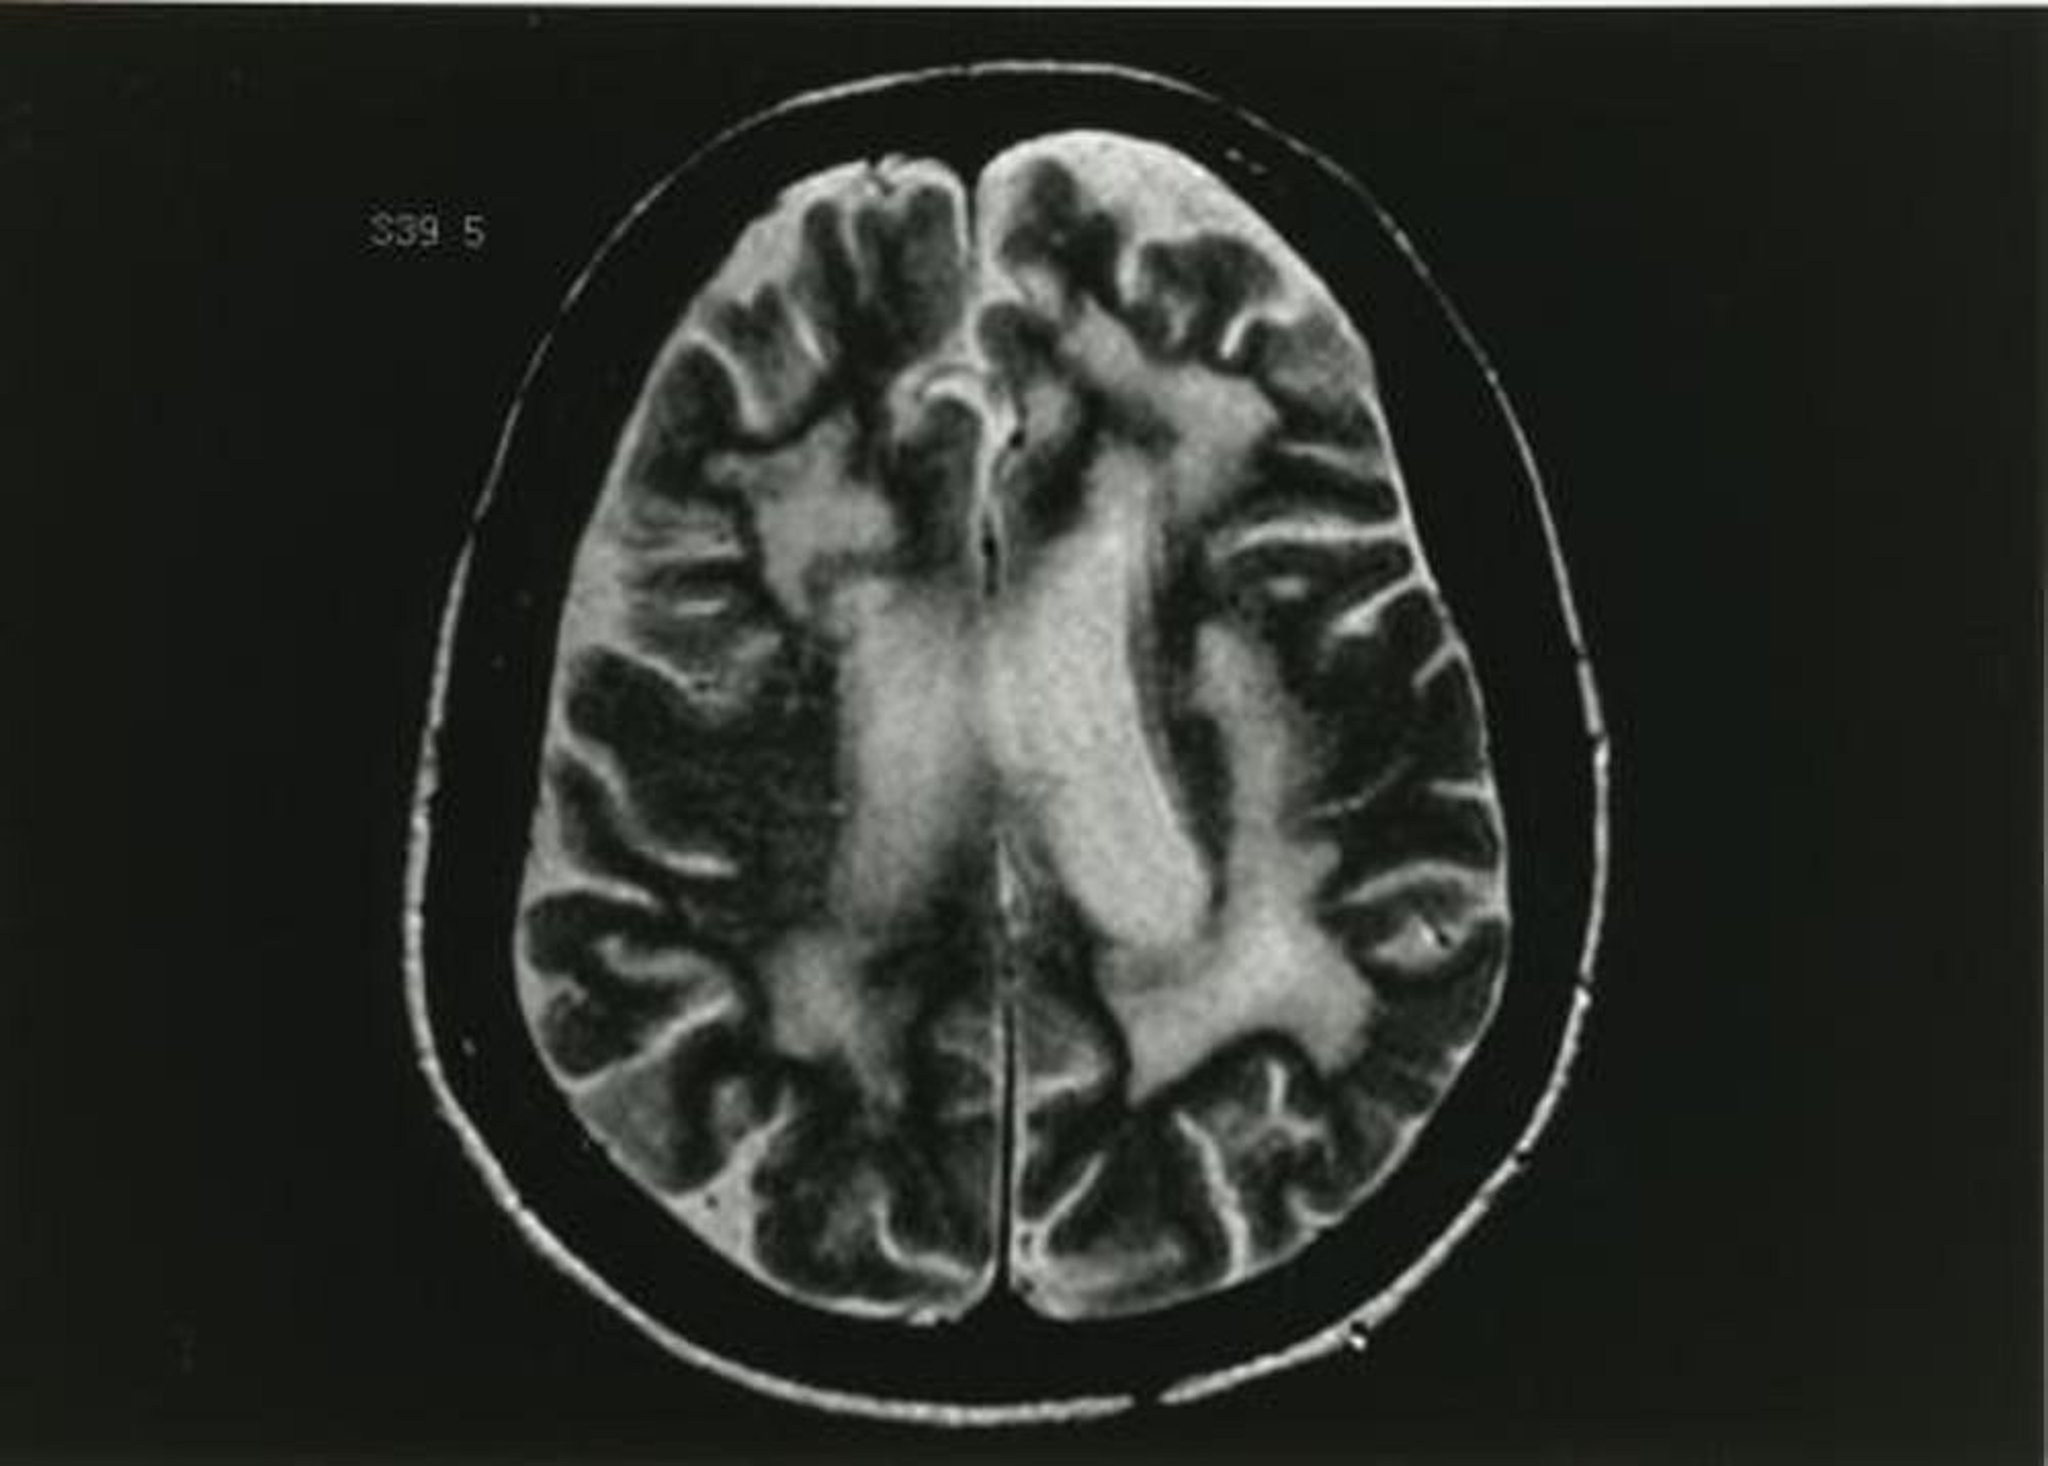

Bệnh não chất trắng đa ổ tiến triển

Hình ảnh MRI trên xung T2 điều chỉnh cho thấy nhiều thay đổi trong chất trắng.

Hình ảnh do bác sĩ John E. Greenlee cung cấp.